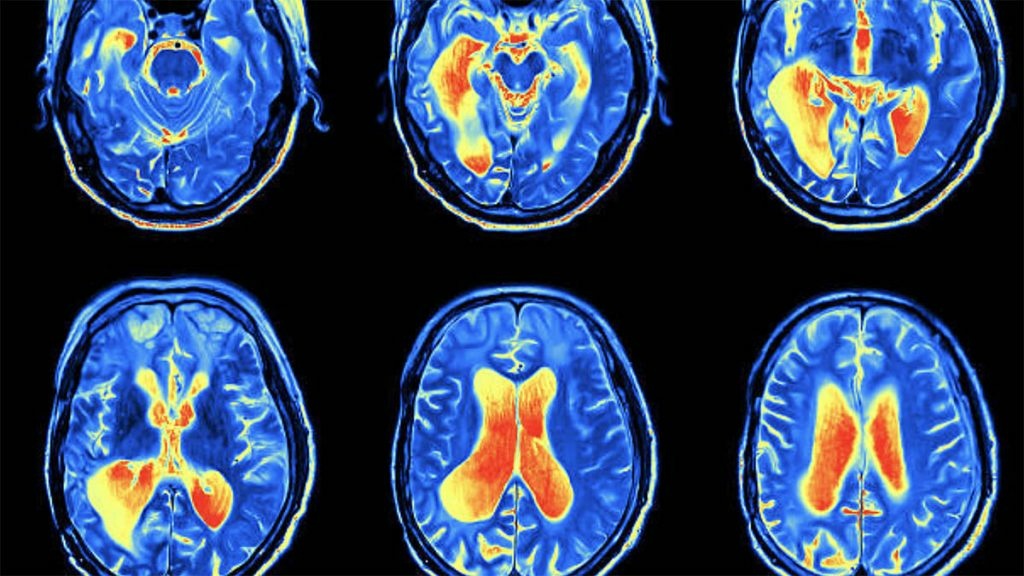

Alzhaimeri është një sëmundje që prek disa zona të trurit përgjegjëse për kujtimet dhe memorien.